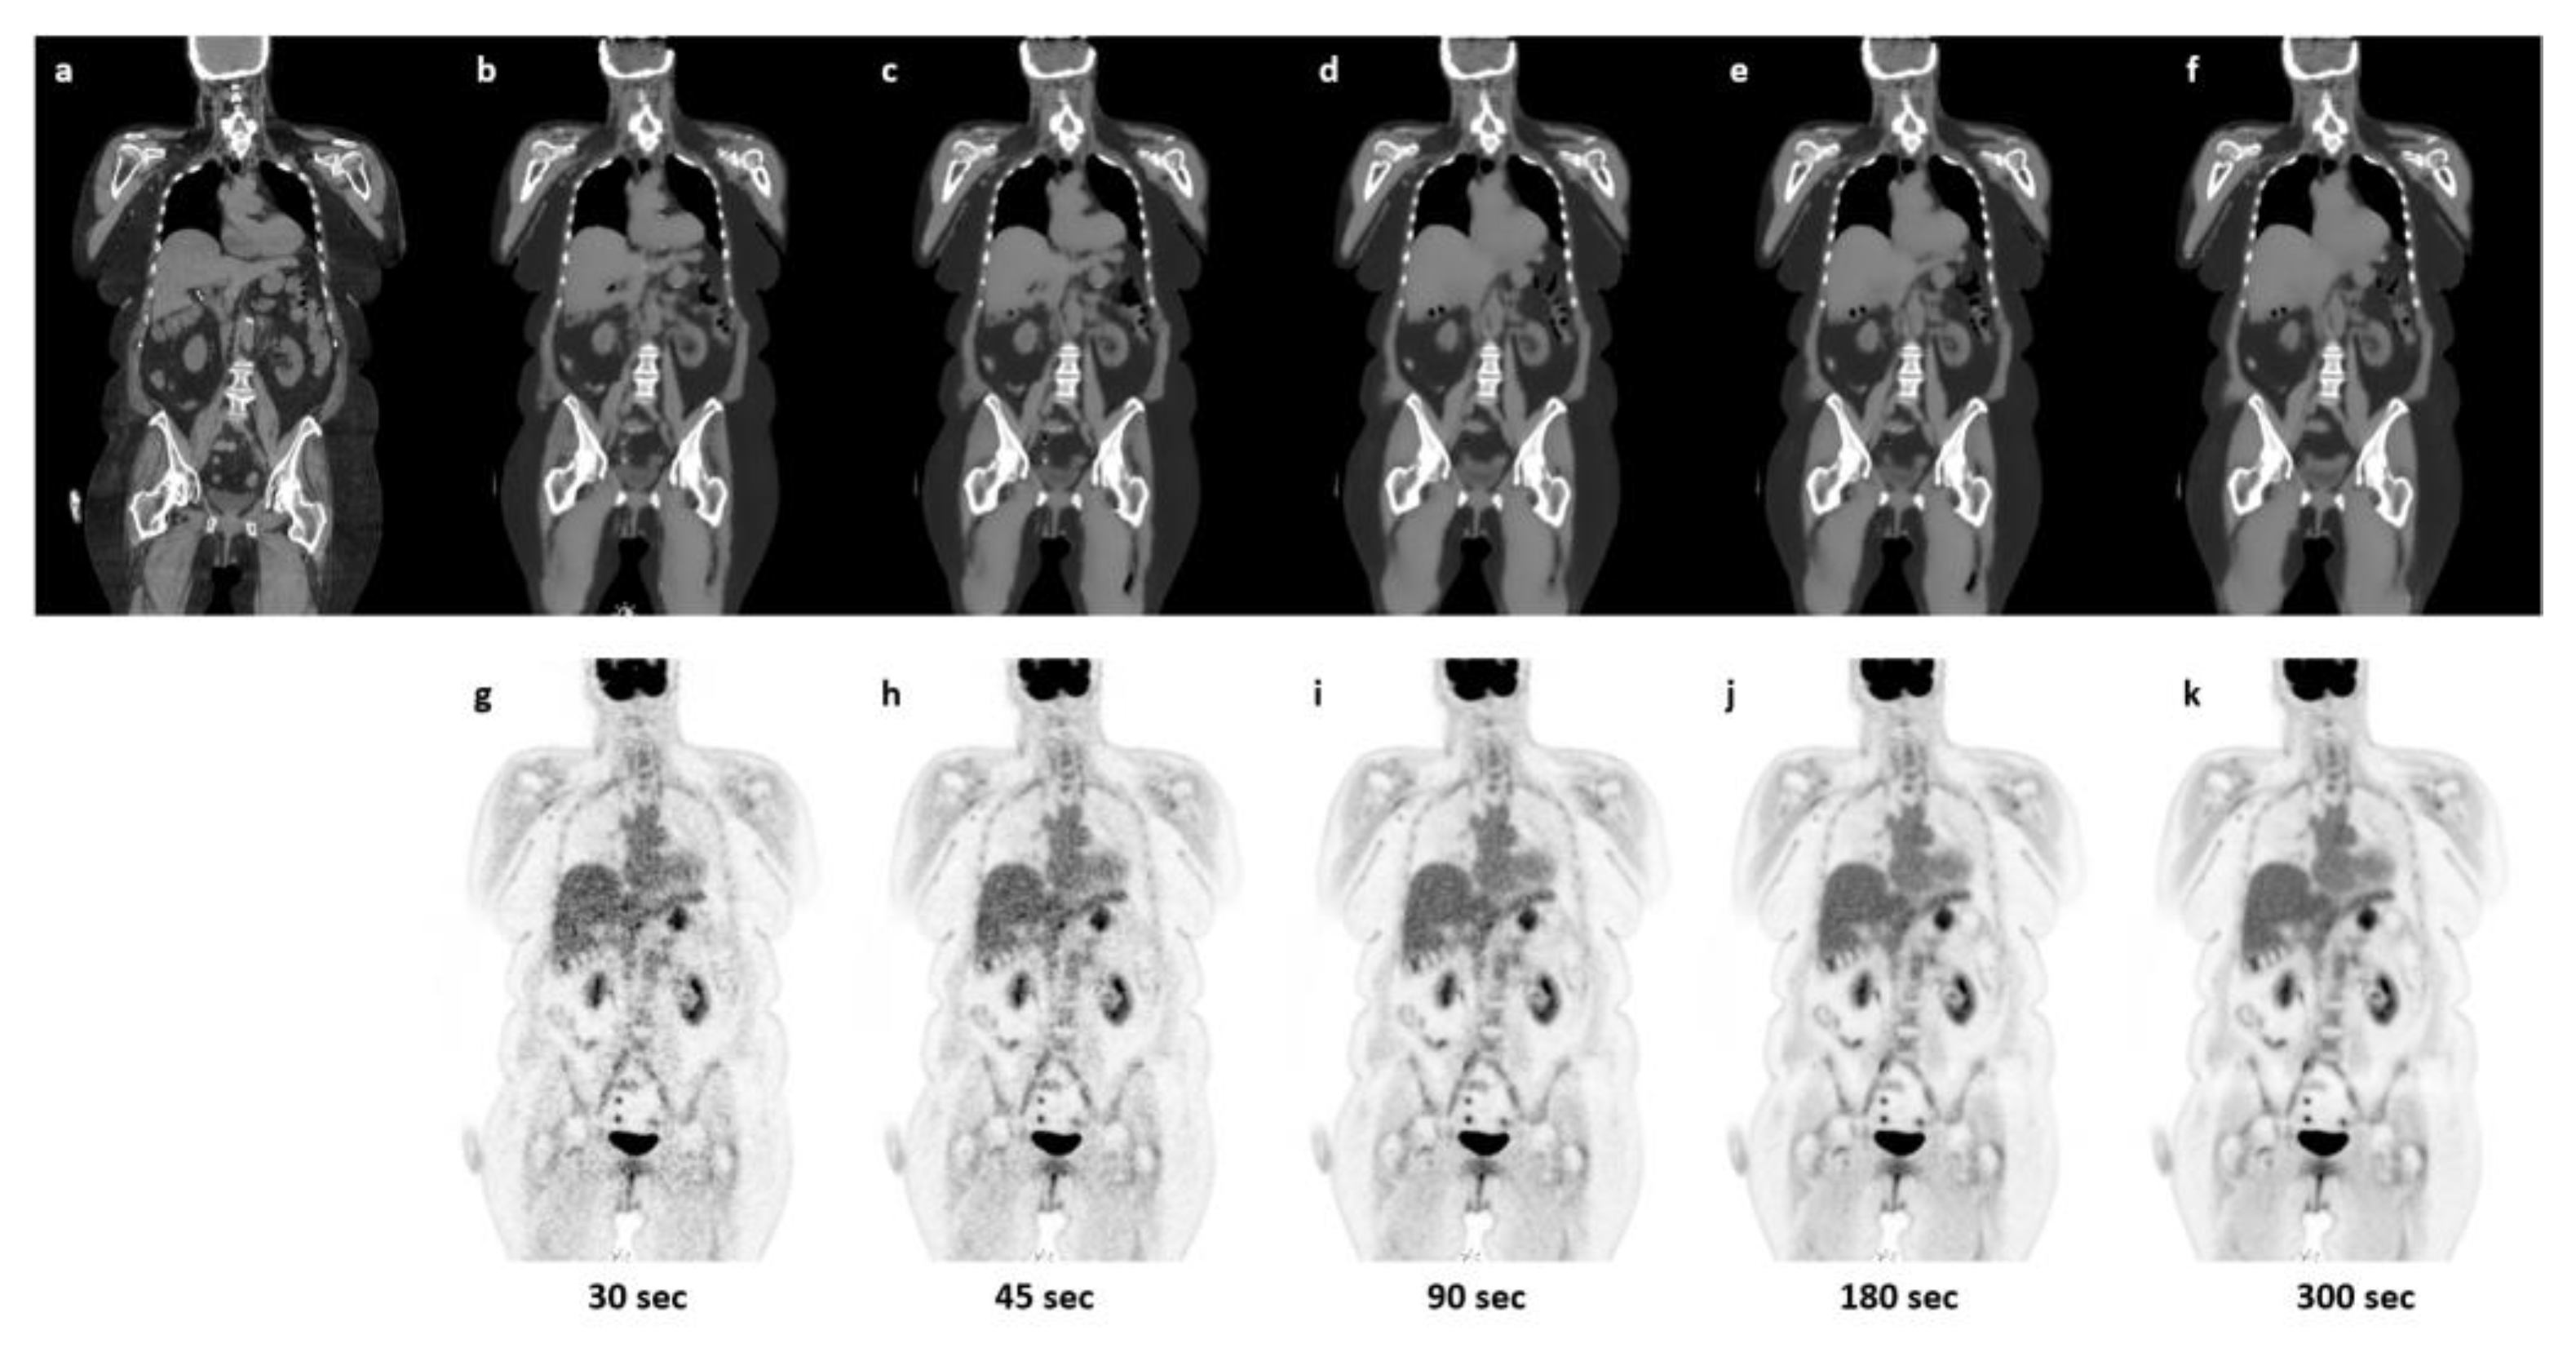

3.1. Qualitative Evaluation

3.2. Quantitative Evaluation